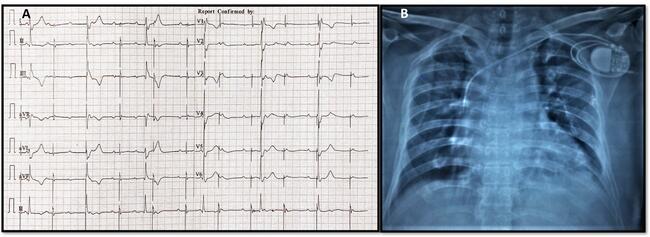

ECG analysis (Figure 2A) showed baseline atrioventricular (AV) dissociation with an atrial rate of 100 bpm. Pacemaker stimulus artifact was noted at regular intervals of 66/min (lower set rate of the VVIR pacemaker) but was not followed by a P wave or QRS complex (capture failure). Intrinsic ventricular escape rhythm was wide (QRS duration 0.16 sec) at a rate of 36 bpm and was not sensed (sensing failure). Chest X-ray (Figure 2B) revealed macro-dislodgement of ventricular lead with tip placed along the superior vena cava-right atrial (SVC-RA) junction, and coiling of leads around the pacemaker generator in its spacious pocket. No obvious lead fracture or insulation breaks were evident. The pacemaker pocket was reopened, and leads were uncoiled, repositioned, and connected to the same generator. Reduction of pocket size to snugly fit the pulse generator, tight suture sleeve fixation of the lead, and extra reinforcement suture fixation of the generator to the pectoral muscle were done.